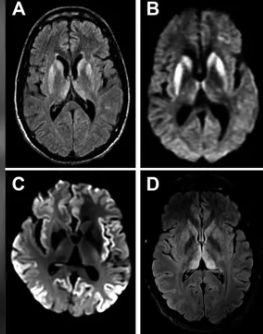

MRI(자기공명영상) 검사 결과 뇌 손상이 발견됐고 추가 검사에서 프리온 단백질 양성으로 밝혀졌다. 프리온은 세포를 둘러싼 세포막에 있으며 세포 통신 및 상호 작용에 관여하는 분자다. 프리온 단백질이 뇌에 쌓이면 주변 단백질이 뒤틀려 신경세포를 손상할 수 있다.

크로이츠펠트-야콥병 환자의 뇌 MRI 영상. Practical Neurology 캡처